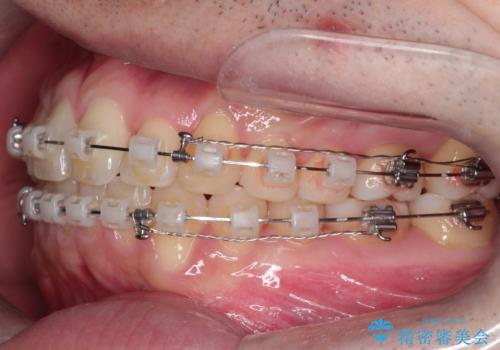

- 矯正装置

- クリア装置

- 治療期間

- 1年6ヶ月